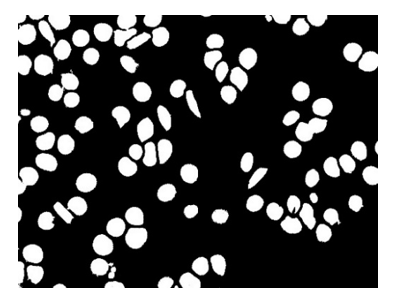

The dataset employed in this study consists of 750 microscopic blood pictures, of which 80-20 ratio is maintained train test split respectively. To enhance the dataset size and improve performance, image augmentation is used. In image Figure 5 preprocessing images are converted from RGB to grey scale after that mean, median and gaussian filter is applied to obtain processed image. Figure 6 processed images are then passed through segmentation step where otsu thresholding in Figures 7 and 8, watershed segmentation, region-based segmentation images several morphological operations are done. Table 1 gives the result of feature extraction.

Figure 7. Binary image

Figure 8. Image after segmentation, noise removal and filling holes using morphological